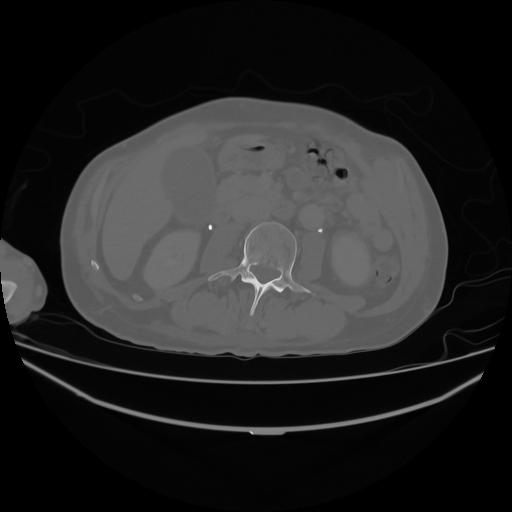

5 CUERPO,CE,Vol,1.0,CUERPO,,